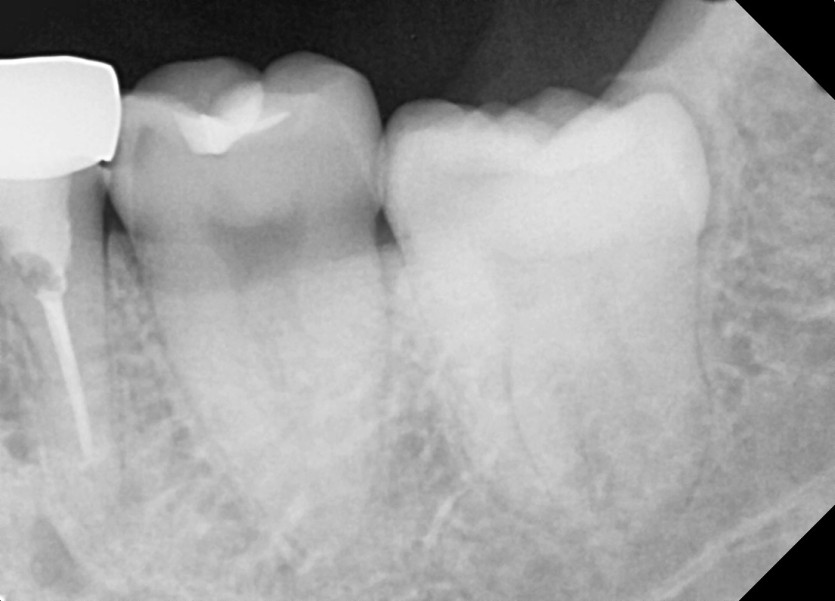

#38 사랑니 발치

구강외과 전문의가 당일 발치했습니다.